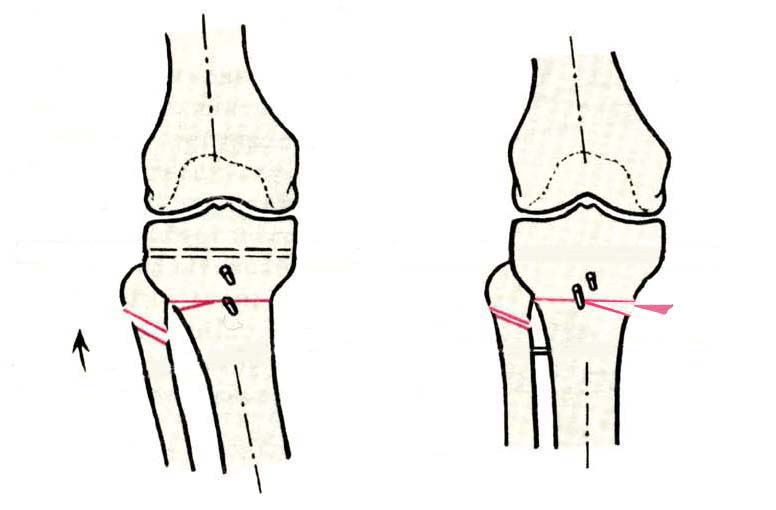

AC> Вот, с учетом и без учета, и на разных уровнях...

AC> Саша Артемьев, может, для данного случая свой вариант нарисуешь?

Из приведнной схемы не совсеим понял что означают разноцветные линии.

И зачем латерализация периферического фрагмента. Я всегда делаю медиализацию. См схему. И для данного случая медиализация подходит как нельзя лучше.

a> Из приведнной схемы не совсеим понял что означают разноцветные линии.

Черные - это нынешняя механическая ось. Красные - это планируемая правильная ось.

a> И зачем латерализация периферического фрагмента.

;-) Читайте Палея. Стр. 114-115.

a> Я всегда делаю медиализацию. См схему. И для данного случая

Медиализация - это чисто эстетический прием, как я понимаю. Поскольку если делать остеотомию ниже вершины деформации, для восстановления оси надо делать смещение по ширине, в данном случае как раз латерализацию.

А вот на схемке без осей - там на разных уровнях (который правильнее?) устранение варуса чисто открытым клином без медиализации-латерализации. Если как-то так сделать - этого недостаточно будет?